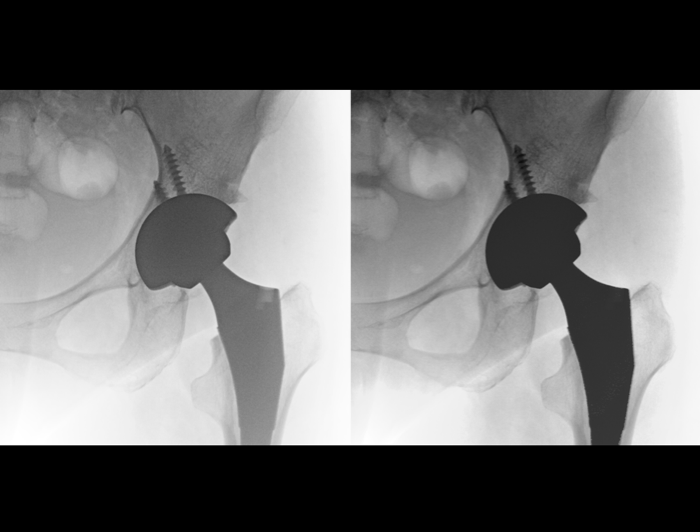

采用芯片级电路单元,大幅缩减信号传输路径,以152μm微像素尺寸与优良晶体结构,实现微剂量高清成像。

200万像素带来2倍于常规的信息采集量,大幅度减少信号损失,清晰捕捉微小解剖结构,提升诊断准确性。

空间分辨率高达3.3lp/mm,多级视野放大,图像细节仍清晰可见。

智能对象识别

智能位置检测、金属检测和运动检测三大智能应用。智能识别患者拍摄位置,实时调节曝光参数,降低金属植入和运动干扰,成就低剂量高清影像。